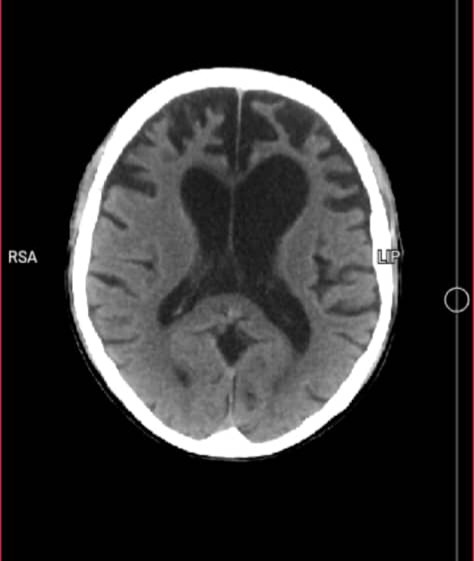

Mi papi ha sido diagnosticado con Hidrocefalia Obstructiva. Esta condición provoca una acumulación de líquido en su cerebro que impide que el oxígeno llegue correctamente a sus neuronas. Debido a esto, su salud se ha deteriorado de forma alarmante y acelerada. Para nuestra familia es doloroso ver cómo la enfermedad le está robando su esencia.